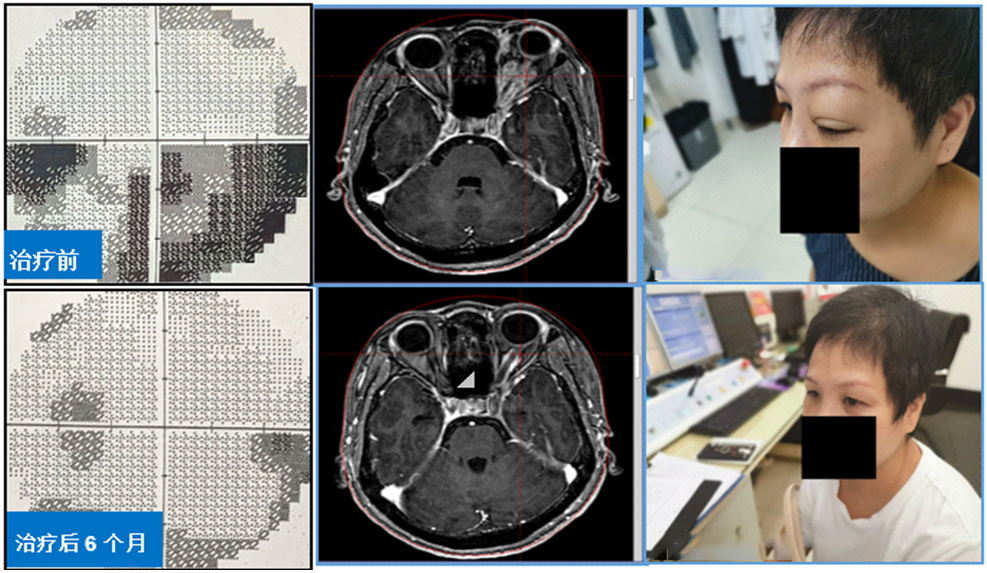

3、伽玛刀治疗眶内球后占位,保全视力视野、改善突眼症状。球后占位患者常伴有突眼、视力下降及视野缺损,伽玛刀分割治疗可快速缓解突眼症状,减轻视神经压迫,再逐步“吃掉”残余肿瘤。该方法是眶内球后占位最有效的治疗手段之一。